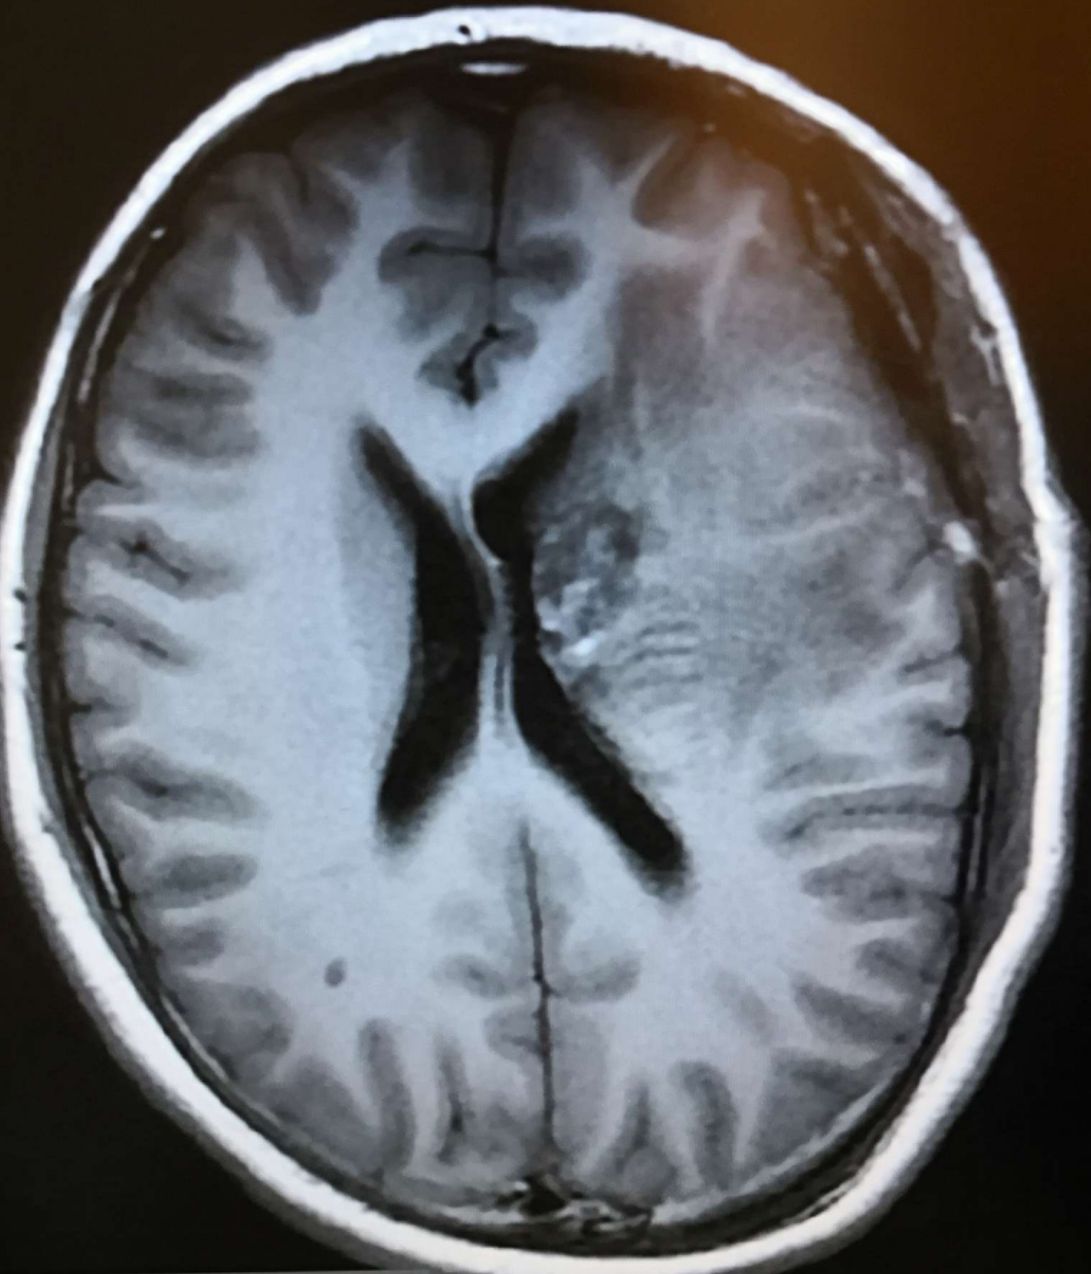

术后头颅MRIT2显示:左侧基底节巨大病灶已经切除,为高、等信号的术野,中线居中,脑室轻度受压。

术后头颅MRIT1显示:左侧基底节巨大病灶已经切除,为低、等信号的术野,中线居中,脑室轻度受压。